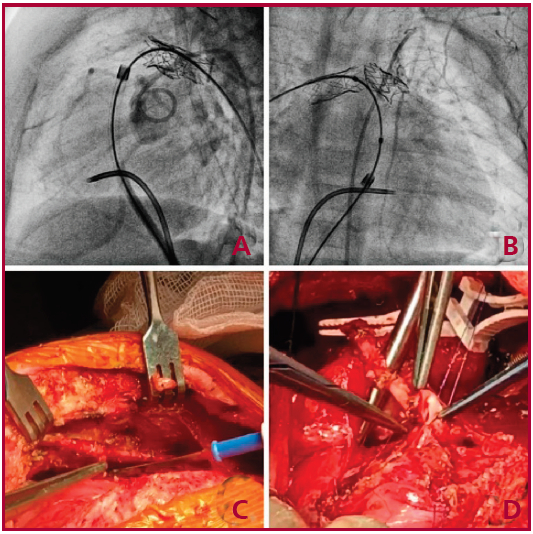

Paciente de sexo femenino nacida en febrero de 2018 con diagnóstico prenatal de doble salida de ventrículo derecho (VD), vasos traspuestos y comunicación interventricular y origen único de arterias coronarias de seno izquierdo. A los 10 días del nacimiento se realizó Switch arterial y cierre de comunicación interventricular. Debido a que la coronaria derecha enlazaba el neotronco pulmonar y que este, además, era ligeramente hipoplásico, la paciente evoluciona con estenosis pulmonar grave residual, que requirió posteriores angioplastias de las arterias pulmonares y plástica quirúrgica del tronco pulmonar y sus ramas principales entre mayo de 2018 y julio de 2019. Dada la progresión de la estenosis pulmonar, se decide nueva cirugía el 11 de febrero de 2020, con el mapeo angiográfico correspondiente (Figura 2 A; B). Se realizó ampliación del tracto de salida del ventrículo derecho, colocación de homoinjerto en posición pulmonar de 15 mm de diámetro, ampliación de las ramas pulmonares con pericardio y realización de CRM con AMI derecha in situ a coronaria derecha proximal (CD) (Figura 2 C; D). La CRM a CD fue por necesidad, para poder ampliar suficientemente bien el tracto de salida del ventrículo derecho y evitar complicaciones con el recorrido de la CD. La paciente fue dada de alta el 15 de febrero de 2020 con buena evolución y presión normal en VD, con función ventricular normal.